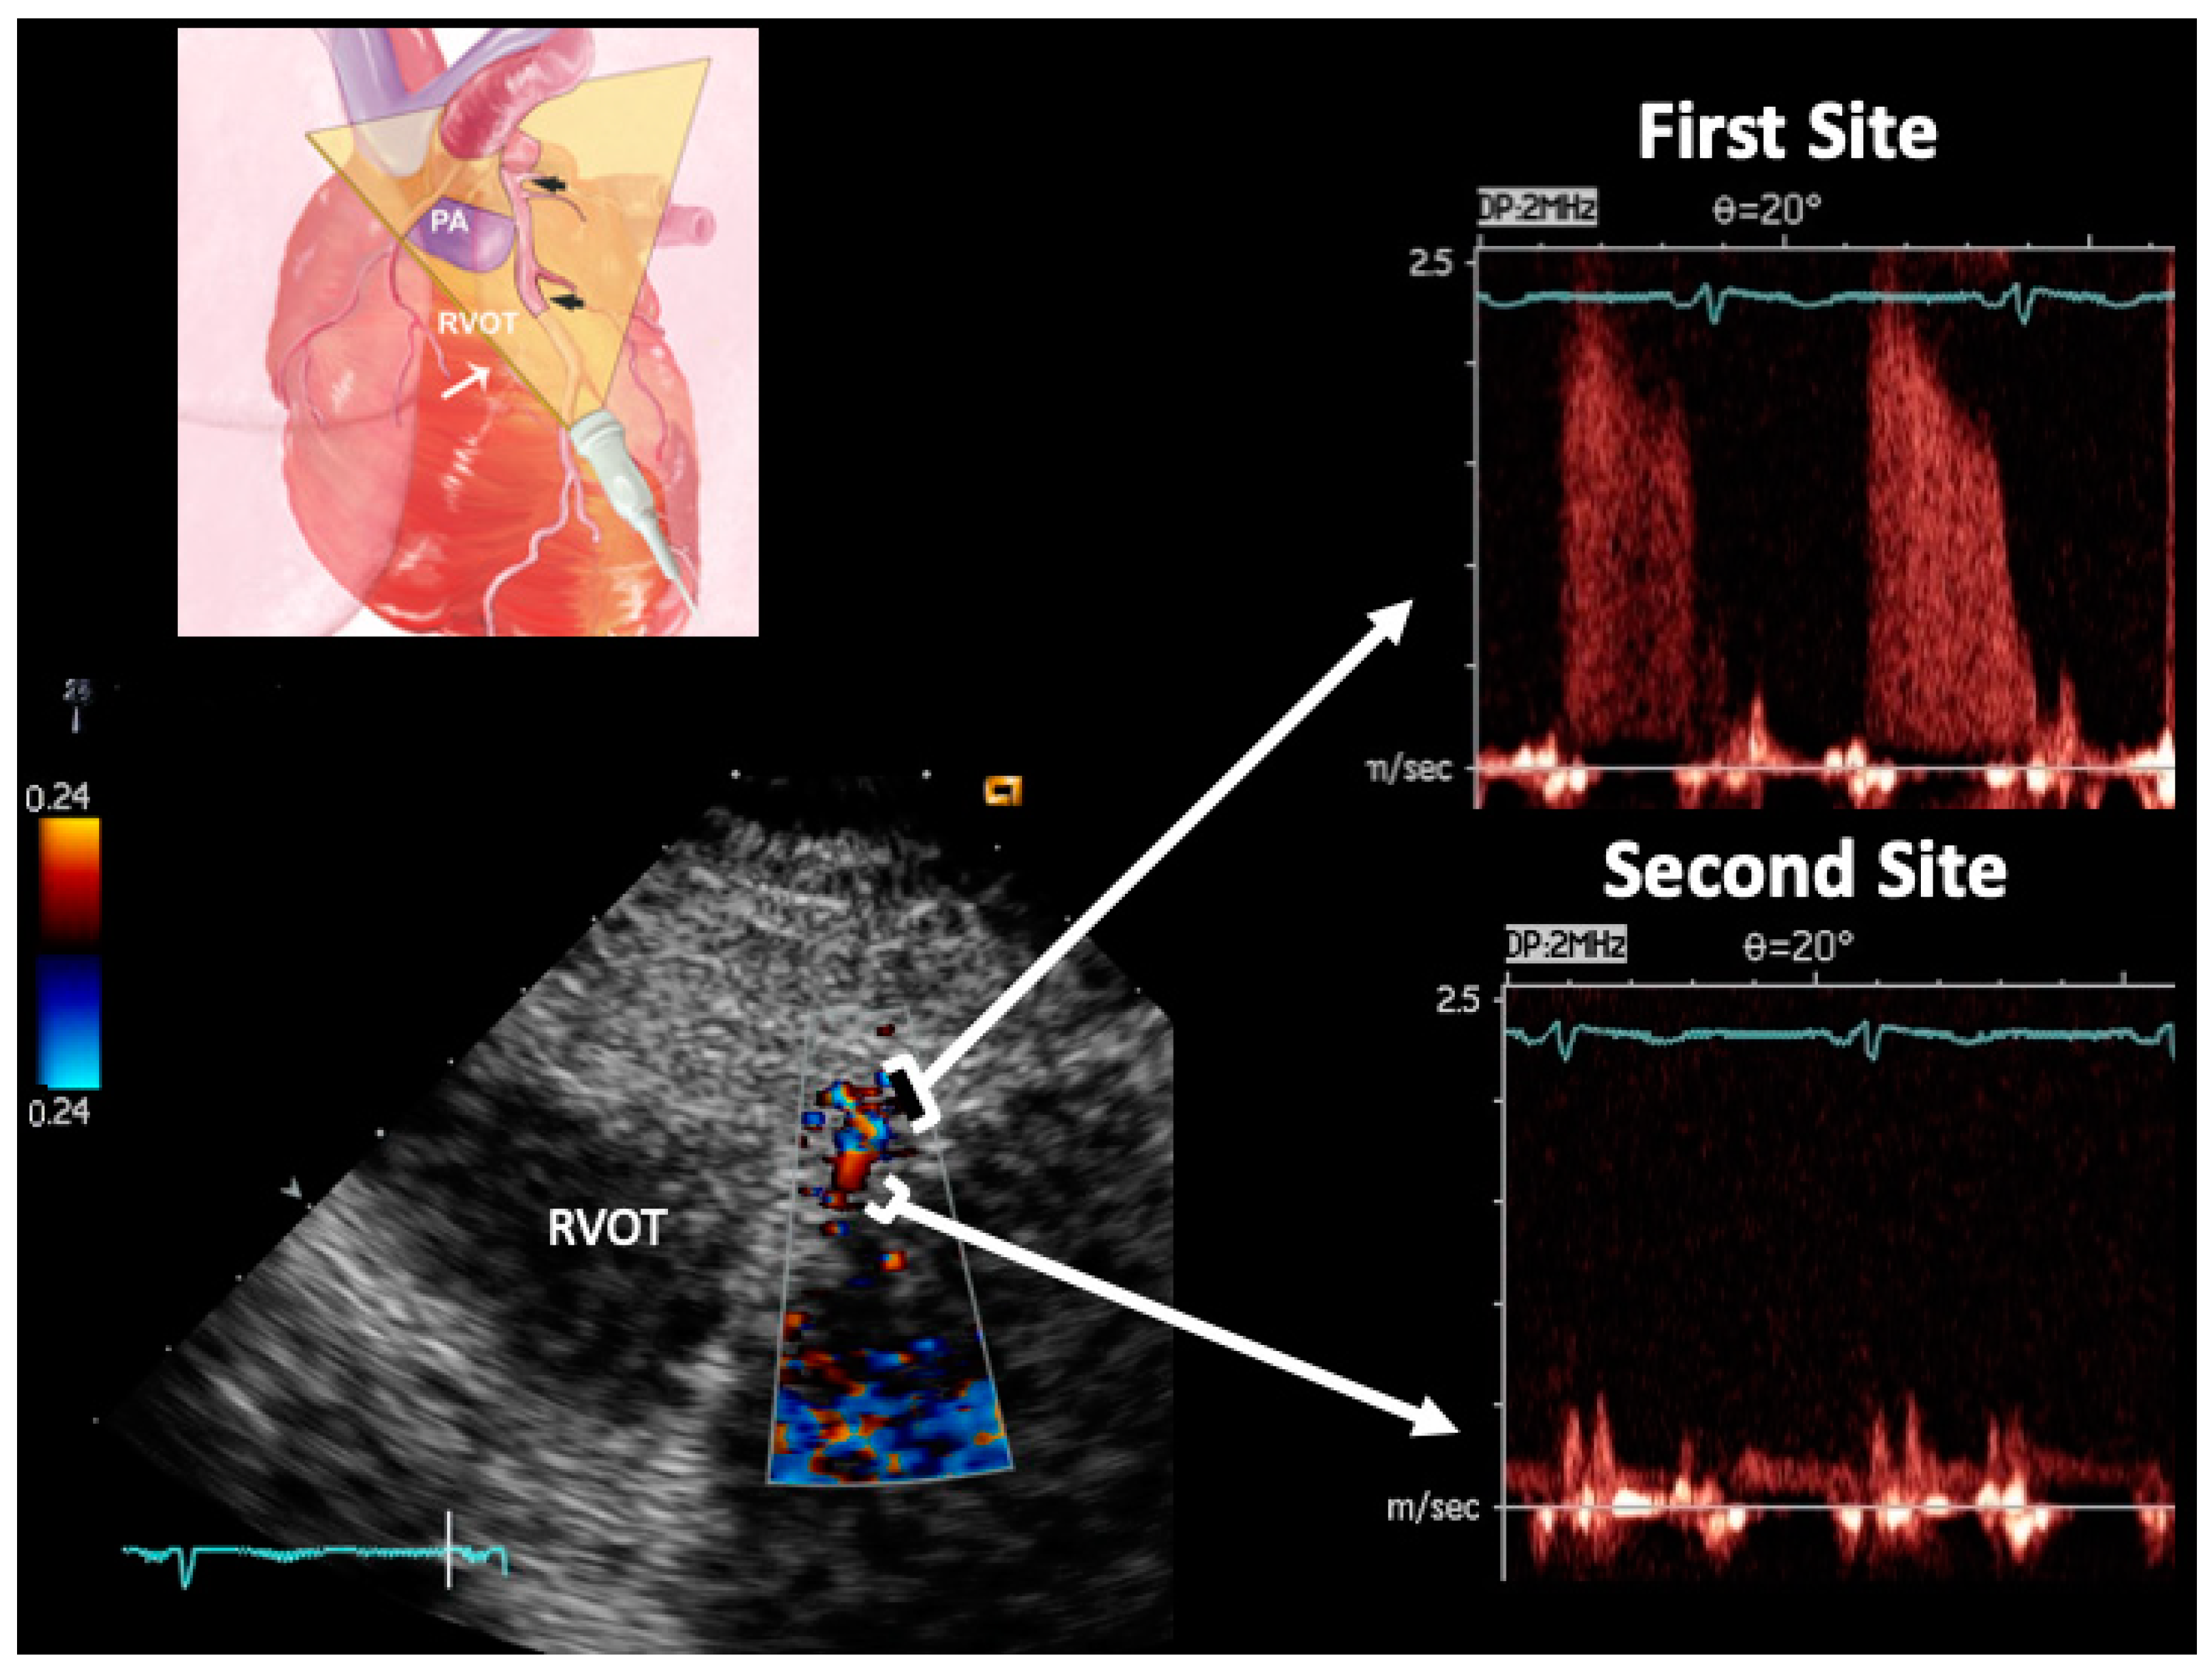

2.4. Ultrasound Plane Orientation

2.7. E-Doppler TTE: Pulsed-Wave Doppler Analysis